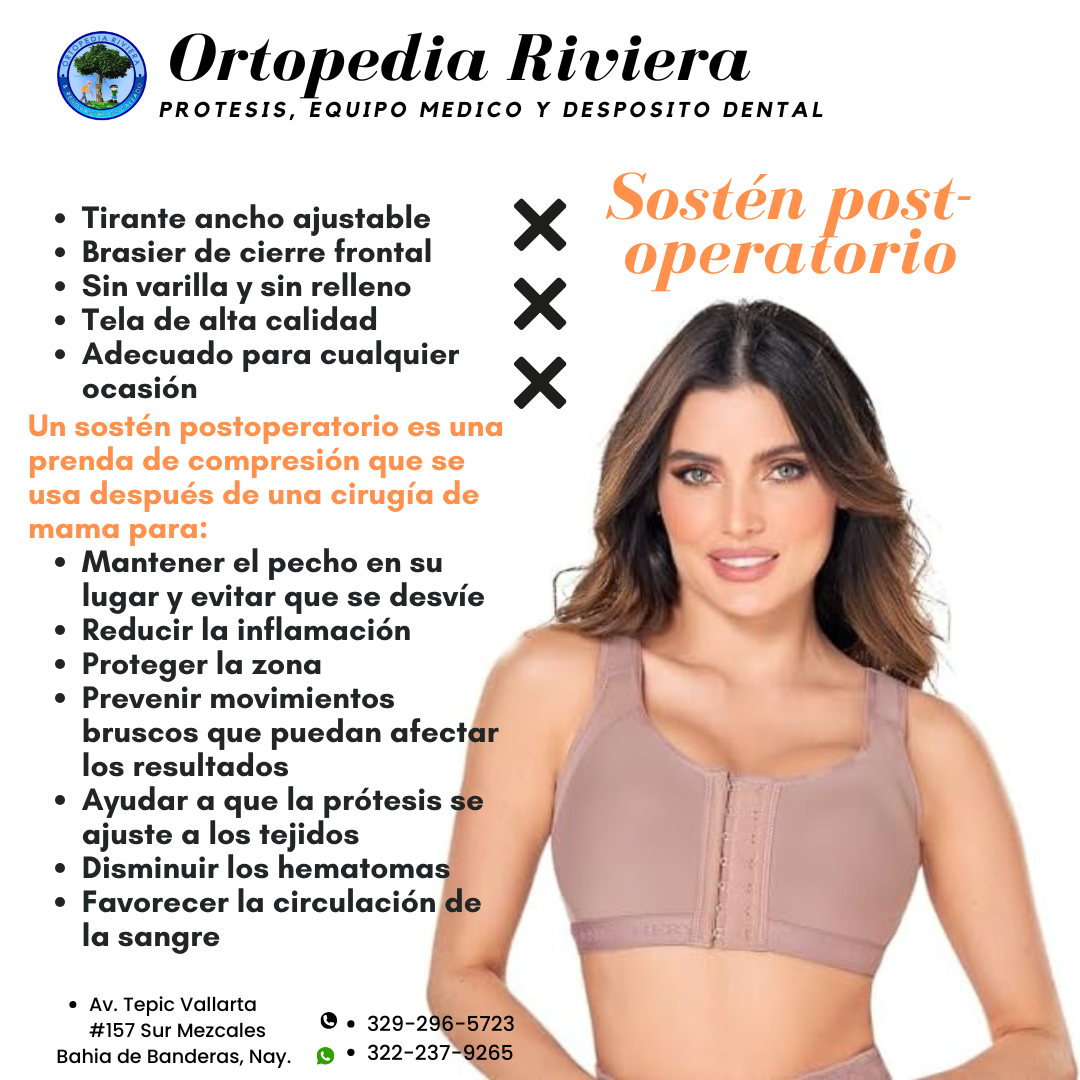

PRÓTESIS

Es un servicio dedicado a la fabricación de prótesis personalizadas de alta calidad utilizando tecnologías de vanguardia. Nuestro equipo de expertos trabaja estrechamente con los clientes para diseñar y producir prótesis que se ajusten perfectamente a sus necesidades y preferencias.